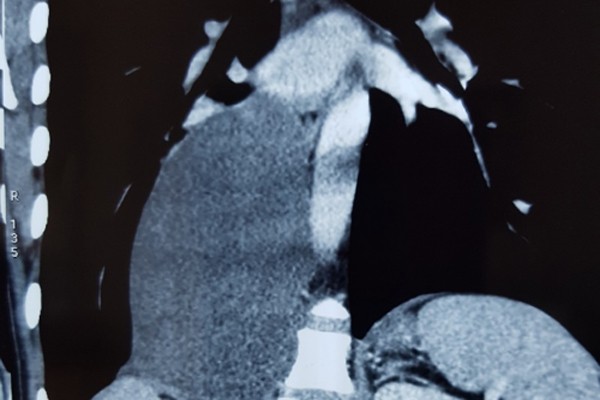

Kết quả chụp cắt lớp vi tính 64 dãy và cộng hưởng từ xác định khối trung thất sau phải có dạng tổ chức đặc kích thước 15x9 cm, đè đẩy vòm hoành phải xuống dưới, chèn ép tĩnh mạch chủ, nhu mô phổi.

Giải phẫu bệnh chẩn đoán là u hạch thần kinh xuất phát từ hạch giao cảm. Bác sĩ chỉ định phải phẫu thuật sớm, càng để lâu khối u càng lớn, chèn ép vào các cơ quan lân cận cản trở tuần hoàn, hô hấp.

TS Phan Lê Thắng, Phụ trách Đơn nguyên Ngoại theo yêu cầu cùng ekip phẫu thuật cho bệnh nhân. Sau gần 2 giờ phẫu thuật, các bác sĩ đã cắt bỏ hoàn toàn khối u thần kinh trung thất sau có đường kính hơn 15 cm, nặng tới 1 kg.

BS Thắng chia sẻ, đây là ca phẫu thuật tương đối phức tạp do kích thước u lớn, choán hết lồng ngực, trường mổ hẹp nên để lấy gọn u rất khó khăn, bác sĩ phải phẫu tích để tránh gây tổn thương mạch máu. Hơn nữa, u phát triển đã lâu nên nhu mô phổi bị chèn ép dẫn đến nhiều nguy cơ sau phẫu thuật.